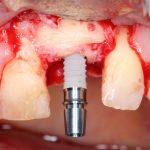

Установка имплантатов

По ряду уже упомянутых выше причин, для решения этой клинической задачи мы выбрали имплантаты Xive. Лунки для них мы уже приготовили. возможную первичную стабильность оценили. Имплантаты мы установили с усилием чуть больше 15-20 Нсм — такого крутящего момента более, чем достаточно, особенно если учесть, что временные коронки будут соединяться между собой.

Подробно о том, что такое крутящий момент и хирургический протокол можно прочитать здесь>> и тут>>, соответственно. Из-за использования специальных индивидуализируемых временных абатментов, имеющих только три положения, нам нужно позиционировать платформу имплантатов по граням. Это очень просто  — мы выводим вырез абатмента TempBase (он входит в комплект поставки) вестибулярно.

После перкуторной проверки стабильности имплантатов и точности позиционирования, мы переходим к следующему этапу — сохранению десневого контура.

Установка имплантатов занимает около двух минут.